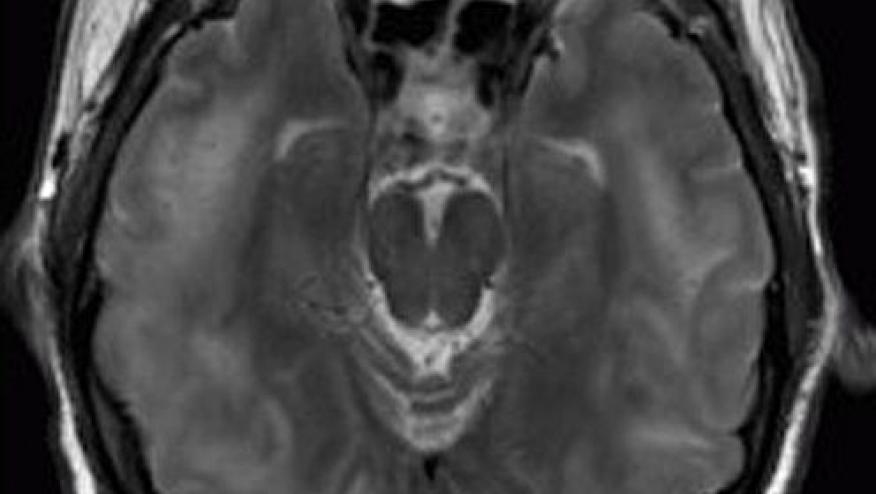

Common manifestations include acute-onset headaches, altered mental status, cortical blindness, seizures, tinnitus and acute vertigo. The diagnosis is established with imaging showing posterior cerebral white matter lesions.

The diagnosis is established by brain magnetic resonance imaging with occipital/posterior cortical and white matter alterations with white matter edema involving the posterior parietal and occipital lobes. Hemorrhagic complications occur in one-quarter of lupus PRES patients, and may have chronic sequelae. Clinical recovery is usually but not always complete.